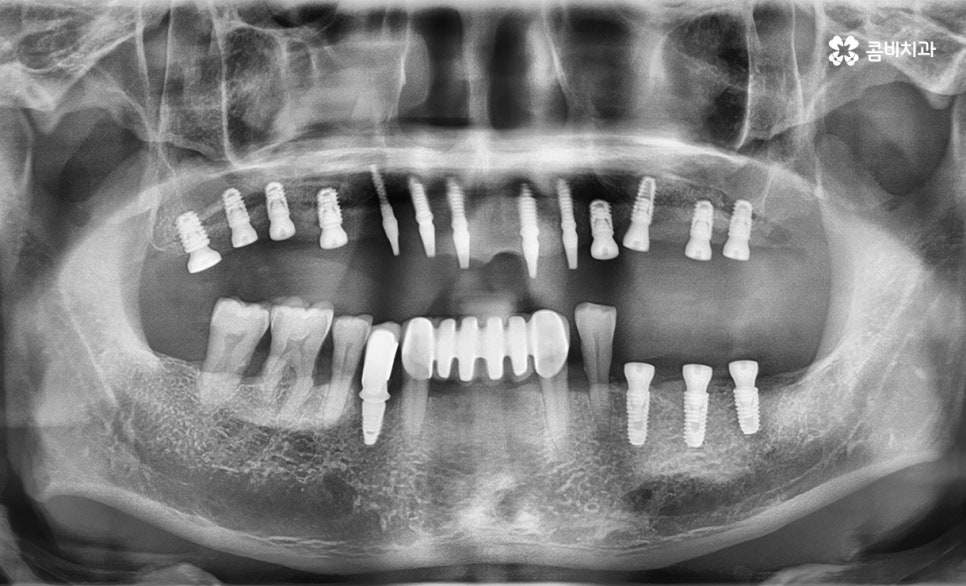

(순차적으로 임플란트 수술 진행이 되어가는 모습)

잇몸뼈가 부족한 경우 뼈이식을 진행하는 경우가 많지만

상악동 막은 매우 얇은 편이기 때문에 자칫 천공으로

이어질 수 있다는 점에서 다른 치아 부위에 비해서도

보다 고난이도의 치료 방법에 해당합니다.

하지만 나이가 들수록 당뇨나 고혈압과 같이 전신질환이

있거나 잇몸뼈의 상태가 좋지 않아서 치료 시에

뼈이식과 같은 과정이 추가적으로 진행되는 경우도

있는 만큼 임플란트 수술은 개인에 따라 적합한

방법으로 진행이 되는 것이 중요하며 관리가 잘 되는 경우에는